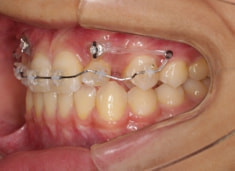

治療開始時

FX(フェイシャルアキシス)は85度なので東洋人の平均値に近く、下顎が前方に過剰成長するリスクは強くはありません。

しかしやはり上顎は劣成長で、下顎が優位な状態ではあります。

上下顎のギャップはありますが、顔面自体の幅径は良好な値を示していますので、スペース不足は拡大することによって解決できポテンシャルはあると考えられます。

左右の非対称もさほど強くありません。